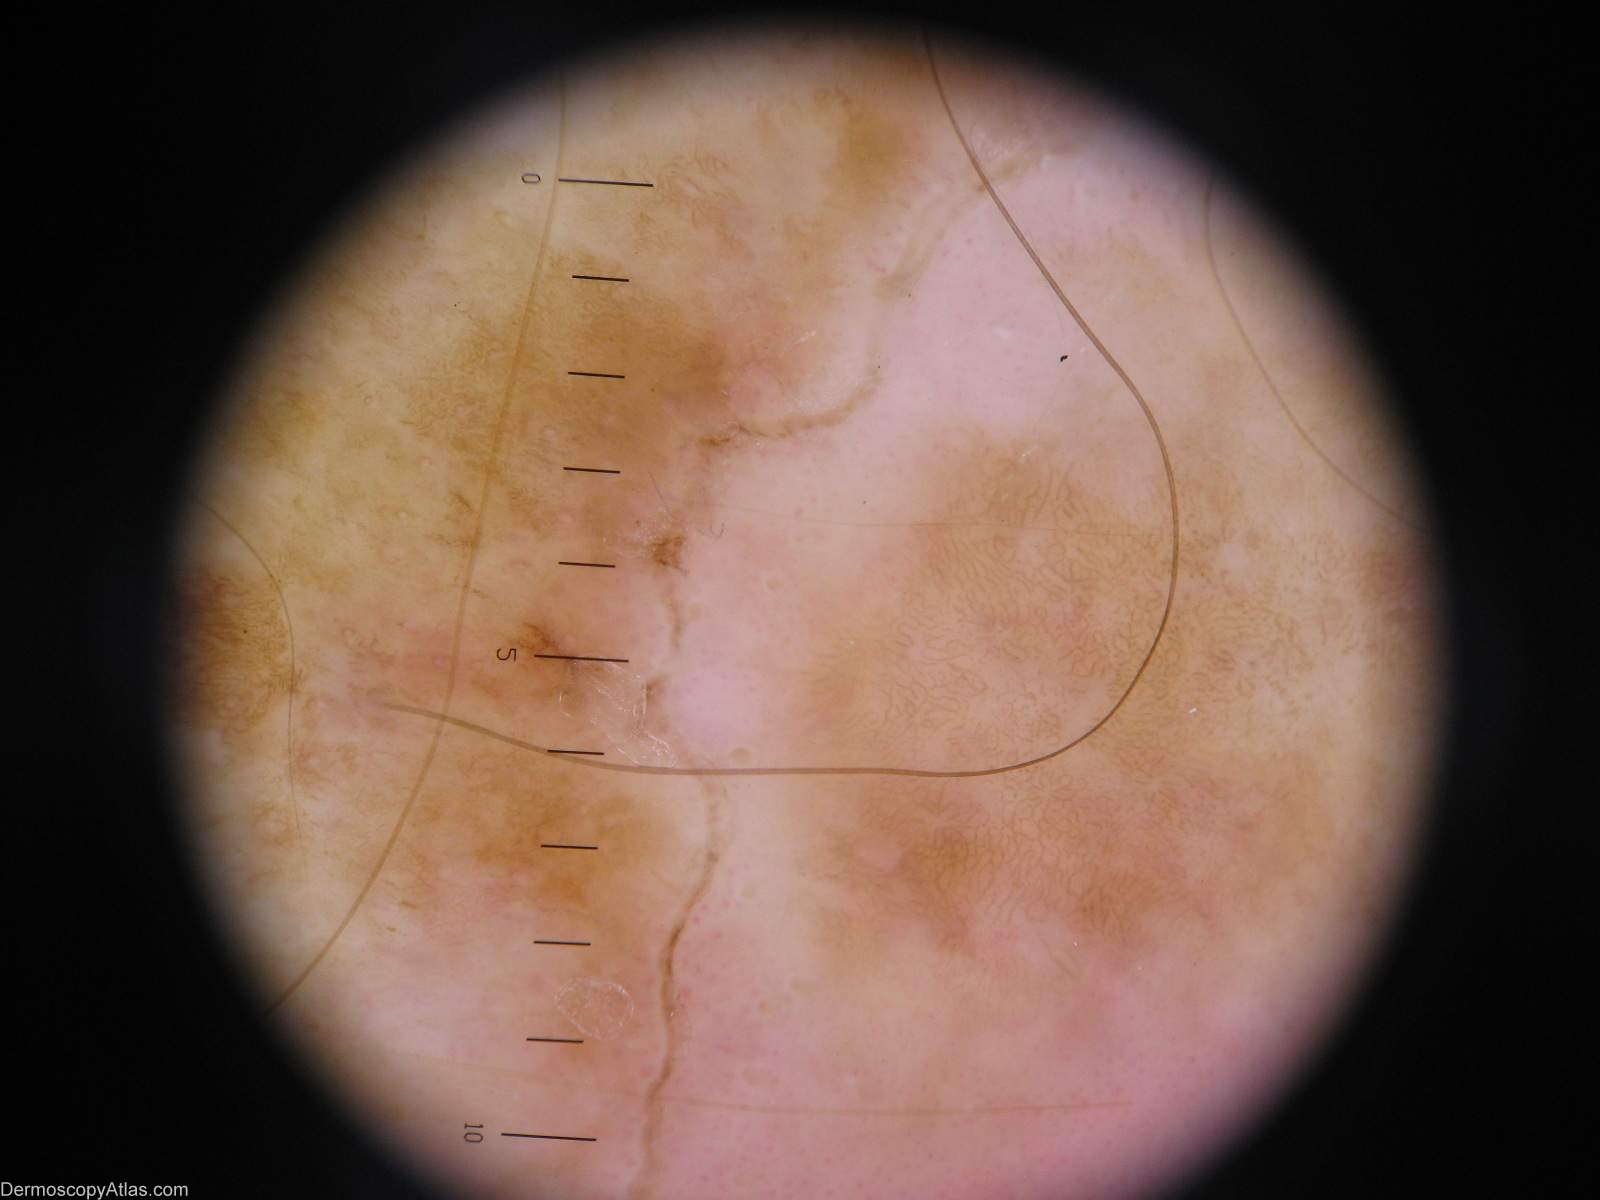

Diagnosis - Porokeratoses

Diagnosis: Porokeratoses